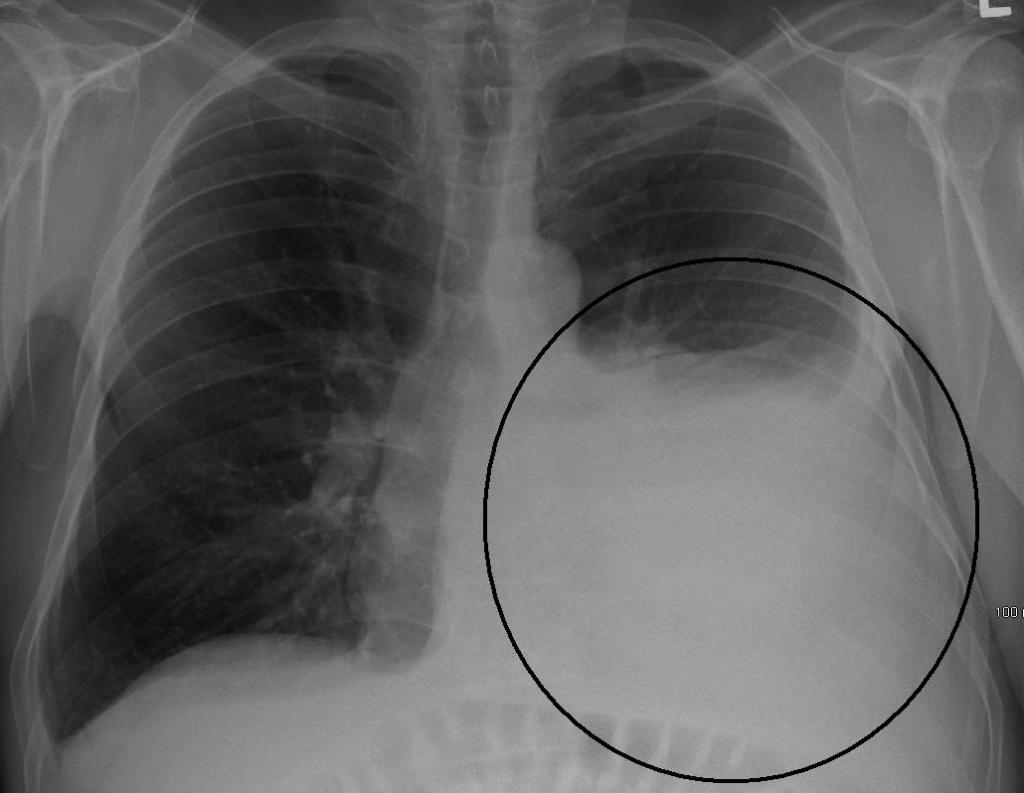

На рентгенографии симптомы выпотного плеврита легких отображаются как интенсивное однородное затемнение в нижних долях органа. Высокое стояние диафрагмы наблюдается при небольшом скоплении жидкости. Средостение смещено к здоровому легкому. При выполнении снимка в латеропозиции (больной ложится на бок) происходит горизонтальное смещение экссудата.

Не выпотной плеврит легких на снимке проявляется интенсивными тенями неоднородной структуры, синусы не определяются. Подвижность плевры резко ограничена.

При перкуссии отмечается ослабление перкуторного звука, причем верхняя граница представляет собой косую линию-Дамуазо, которая хороша видна на рентгенографии. При выслушивании легких фонендоскопом отчетливо слышен шум трения плевры, он похож на скрип снега. Дыхание в местах скопления жидкости резко ослаблено.